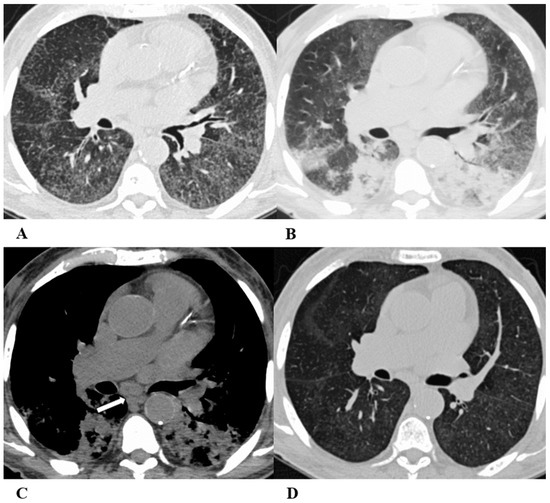

Figure 5.

Obliterative bronchiolitis (OB). Obliterative bronchiolitis, also known as bronchiolitis obliterans, is an uncommon lung manifestation associated with ICI therapy. OB represents a type of bronchiolitis characterized by the concentric luminal narrowing of the small airways due to submucosal and peribronchiolar inflammation and fibrosis. HRCT scans, especially several weeks after the acute onset, can show the presence of sharply defined areas of decreased lung attenuation with reduced caliber vessels, giving a mosaic attenuation pattern, better seen on expiratory scans, if necessary. Bronchial wall thickening and centrilobular opacities are common, while advanced findings such as reticulations and traction bronchiectasis are poorly described because of the early diagnosis of drug-induced toxicity [18,19].

In the past, the bronchiolitis model was not considered a manifestation of therapeutic toxicity due to its similar appearance to the infectious and inflammatory causes of bronchiolitis. However, suspicion of this condition as an ICI-related pattern should arise when no infectious symptoms are present and should be confirmed through imaging; it is necessary to demonstrate the resolution of the pathological findings either by suspending ICIs or by demonstrating this after treatment with steroids.

Moreover, to differentiate bronchiolitis from other causes of infection, there are further features to consider; aspiration pneumonia typically occurs in the dependent lung regions with fluid stagnation in the bronchi lumen and in the presence of esophageal ingestions, while other infective pneumonias are often clinically distinguishable.

(A–D) A 57-year-old man with gastric cancer and splenic metastasis treated with pembrolizumab. Cough and moderate dyspnea affected the patient two months after the beginning of immunotherapy.

Axial chest CT scans demonstrate, in the paramediastinal region of the left upper lobe, subtle thickening of the bronchiolar walls associated with an area of modest ground-glass with rare centrilobular micronodules (A) and bilateral thickening of the bronchial walls (B). In the middle lobe and lingula, there is the presence of multiple small centrilobular opacities with initial thickening of the interlobular septa, which better defines the anatomy of some contiguous secondary lobules (white arrows (B)). Bilaterally, especially in the lower left lobe, there is the presence of other patchy areas of pulmonary opacity similar to those found in other inflammatory–infectious processes (black arrows (B)).

The chest CT performed 20 days after pembrolizumab interruption showed a marked improvement in lung condition (C,D).